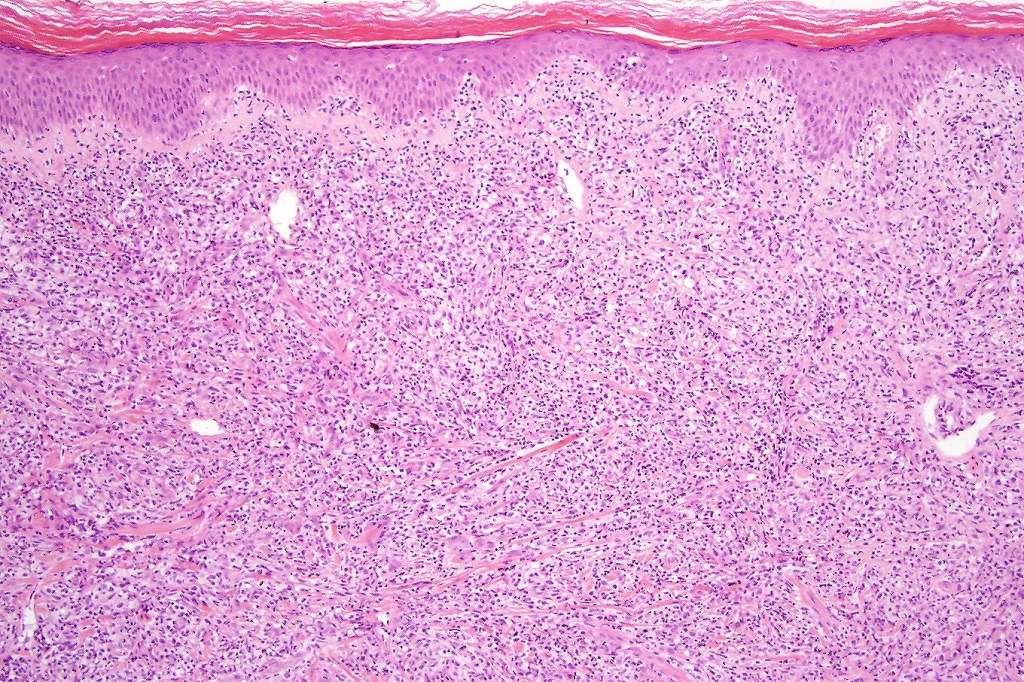

Histological features

The histological hallmark of mycosis fungoides is the presence of large atypical lymphocytes with a convoluted/cerebriform nuclear border (Sézary cells). These may be found at the epidermal-dermal jnuction and as collections within the epidermis (Pautrier microabscess). These are most easily found in plaque stage disease. The epidermal component can be subtle in patch stage disease and is often lost in tumor stage dsease. The classification into patch, plaque & tumor stage disease is less helpful histologically as the features merge from one to the other. It is all a matter of degree.

Plaque Stage Disease

•Compact hyperkeratosis & patchy parakeratosis

•Acanthosis

•Psoriasiform hyperplasia common

•Epidermotropism is often marked with conspicuous Pautrier microabscesses

•Lichenoid variant & poikiloderma atrophicans vasculare

•Variable folliculotropism (+/- mucinosis) & syringotropism

•Coarse collagen bundles in papillary dermis

•Superficial band-like dermal infiltrate of atypical lymphocytes, eosinophils, plasma cells & histiocytes